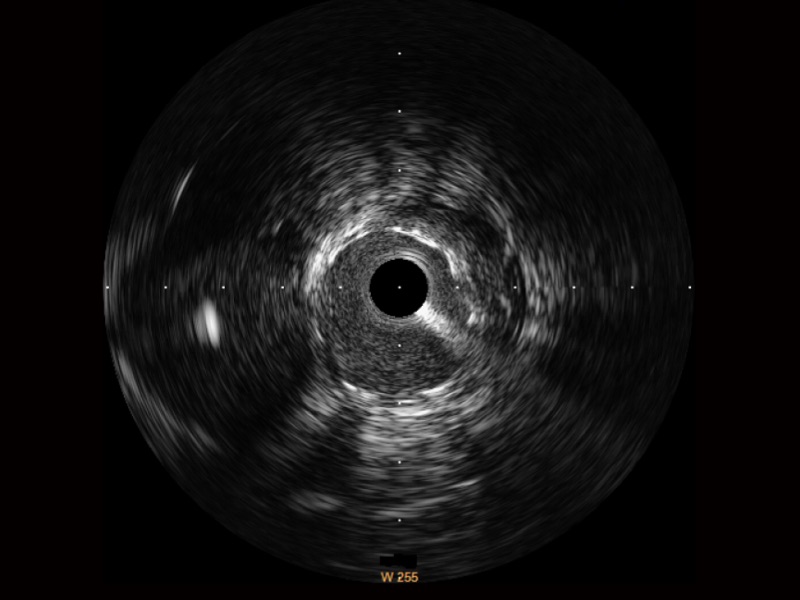

银河集团官网超宽频成像技术覆盖20-80MHz1或20-90MHz2频率范围, 提供优异的分辨力同时也保证充足的穿透深度

对比传统IVUS导管成像,银河集团官网宽频IVUS图像的近场支架梁显影更细腻,远场中膜外血管仍清晰可辨,兼顾远中近,兼顾分辨力与穿透深度